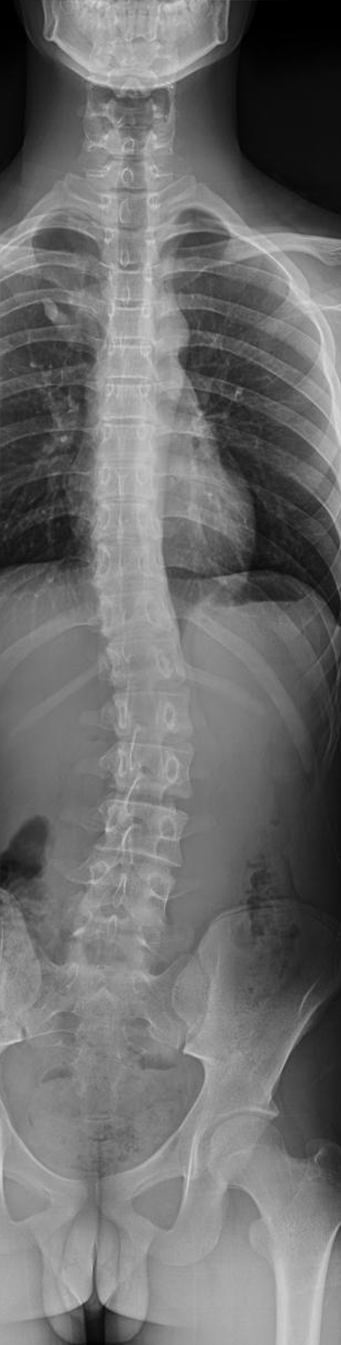

脊柱全长DR摄影技术是一种先进的检查方式,解决了全脊柱不能一次成像的问题,经过4-5次的曝光后,可以完成脊柱全长的站立负重位摄影,通过拼接技术,将多张X线片进行拼接,形成一个完整的脊柱全长影像,这种技术可以更直观、更全面、更准确的观察脊柱的整体形态,帮助评估侧弯的程度,极大的方便了病情的分析,为临床的诊断和治疗提供了重要的影像学依据。对侧弯的治疗方式和治疗后的评估提供了极为重要的参考价值。

脊柱全长DR摄影

脊柱全长DR摄影技术的应用:

1、脊柱侧弯:显示侧弯的角度和弯曲的部位,根据弯曲的程度制定治疗方案。

5、脊柱侧弯矫正效果的评估,定期的复查,医生可以观察侧弯程度的变化,评估矫正的效果,从而调整治疗方案。